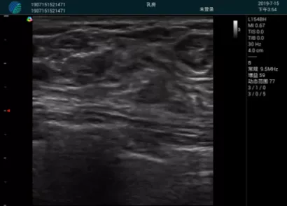

清晰顯示腺體內(nèi)低回聲快影,邊界清晰,包膜較光滑

確定進(jìn)針路徑并實(shí)時(shí)監(jiān)測抽吸針與腫塊位置關(guān)系

抽吸針進(jìn)入腫塊內(nèi)部進(jìn)行旋切

抽吸過程中可見腫塊明顯縮小,并根據(jù)腫塊位置改變針道位置

抽吸旋切后再進(jìn)行超聲復(fù)查,原腫塊區(qū)域未見殘留組織及出血